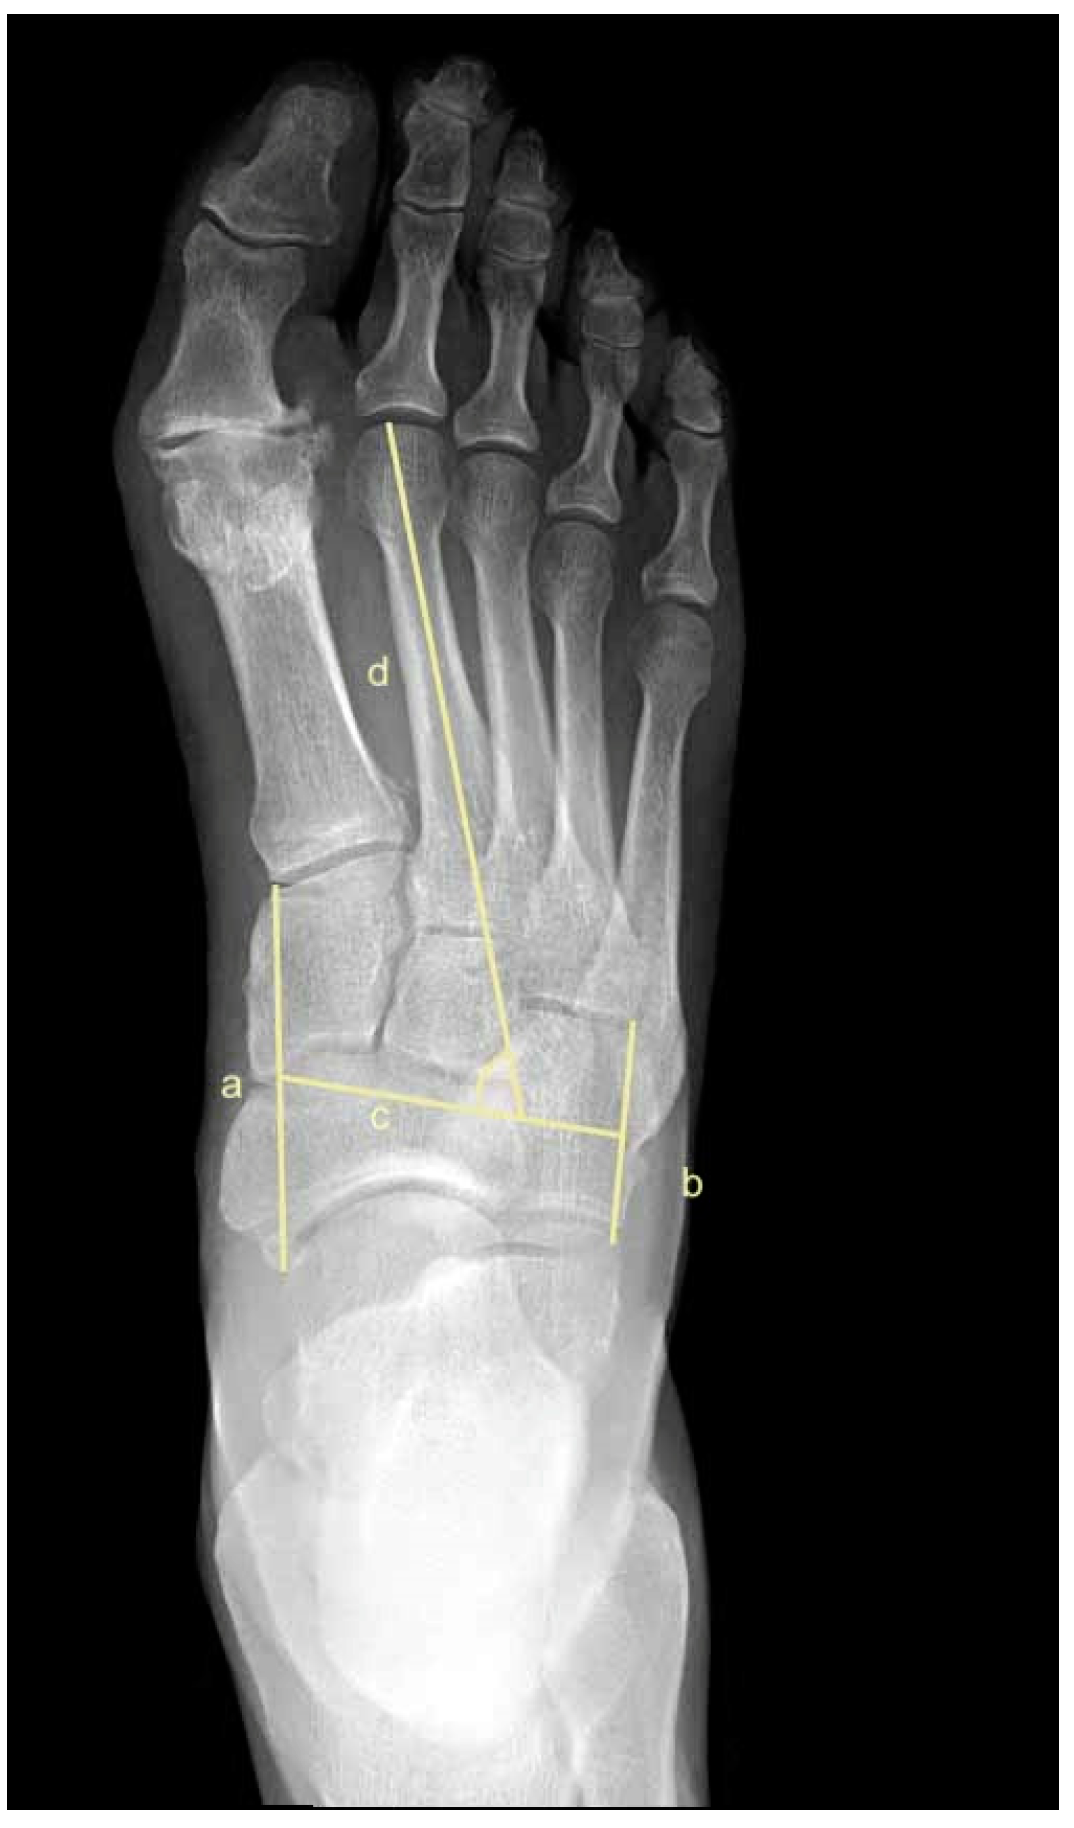

2.5. Metatarsus Adductus Measurements

- Sgarlato, T.E. Compendium of Podiatric Biomechanics; California College of Podiatric Medicine: San Francisco, CA, USA, 1971. [Google Scholar]

- Weissman, S.D. (Ed.) Biomechanically acquired foot types. In Radiology of the Foot; Williams and Wilkens: Baltimore, MD, USA, 1989. [Google Scholar]

- Gentili, A.; Masih, S.; Yao, L.; Seeger, L.L. Pictorial review: Foot axes and angles. Br. J. Radiol. 1996, 69, 968–974. [Google Scholar] [CrossRef]

- Ganley, J.V.; Ganley, T.J. Metatarsus adductus deformity. In Comprehensive Textbook of Foot Surgery, 2nd ed.; Wilkins, W., Ed.; Williams and Wilkens: Baltimore, MD, USA, 1992; pp. 829–852. [Google Scholar]

- Engel, E.; Erlick, N.; Krems, I. A simplified metatarsus adductus angle. J. Am. Podiatry Assoc. 1983, 73, 620–628. [Google Scholar]

- Simons, G.W. Analytical radiography of club feet. J. Bone Jt. Surg. Br. Vol. 1977, 59, 485–489. [Google Scholar] [CrossRef] [PubMed]

- Laaveg, S.J.; Ponseti, I.V. Long-term results of treatment of congenital club foot. J. Bone Jt. Surg. Am. Vol. 1980, 62, 23–31. [Google Scholar] [CrossRef]

- Kilmartin, T.E.; Flintham, C. Hallux valgus surgery: A simple method for evaluating the first-second intermetatarsal angle in the presence of metatarsus adductus. J. Foot Ankle Surg. 2003, 42, 165–166. [Google Scholar] [CrossRef]

- Dawoodi, A.I.S.; Perera, A. Radiological assessment of metatarsus adductus. Foot Ankle Surg. 2012, 18, 1–8. [Google Scholar] [CrossRef]